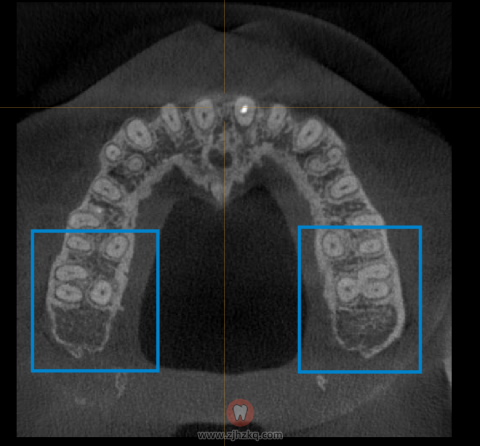

想要把牙齿往后推,首先得保证磨牙后面的牙槽骨有足够的空间。

而且这个空间是三维方向的,不仅要在长度上,在宽度上也要有足够的地方能容纳磨牙的后移。

因为磨牙的牙根比较粗壮,后面的牙槽骨不一定能装得下。

所以,在选择推磨牙方案时,一定要提前拍CT确认牙槽骨的骨量。